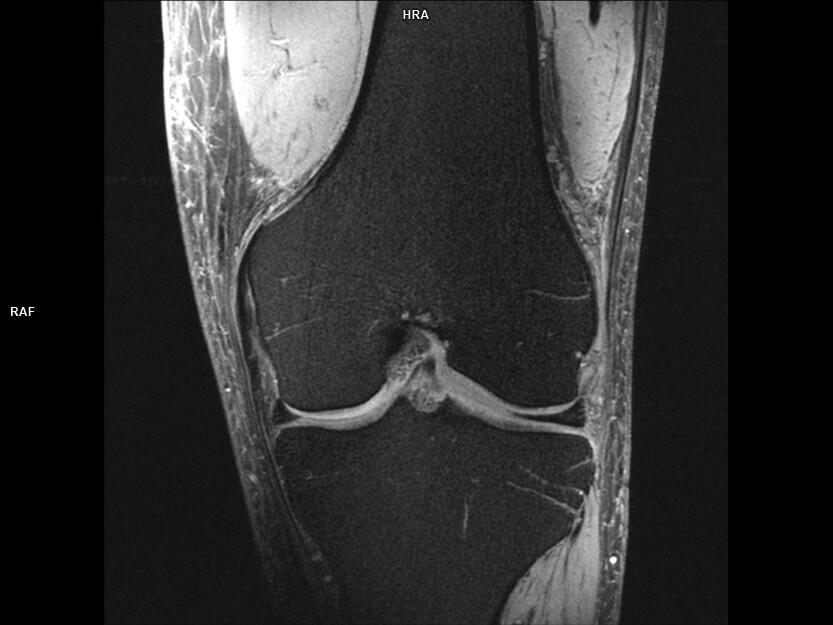

Coronal T1 TSE FS-MAGNETOM Terra

Coronal T1 TSE FS-MAGNETOM Terra/Coil-Knee 28/Resolution-416/Scan Time-2:32/Aceleration-p2